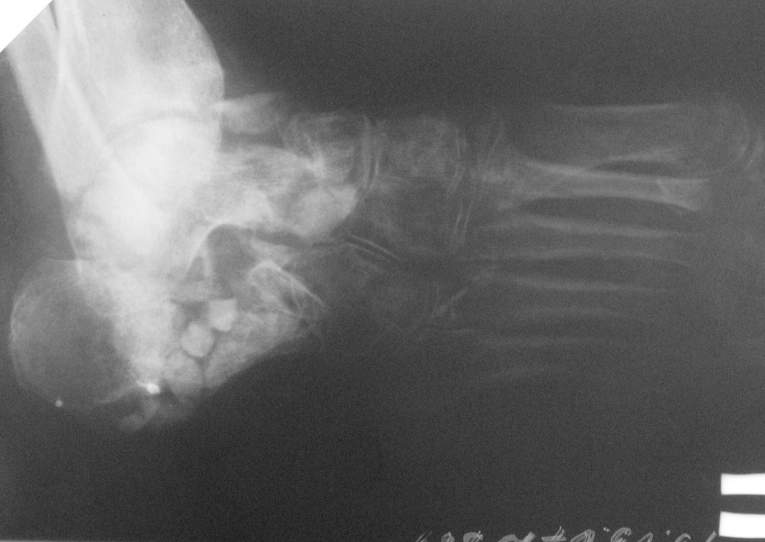

Re: Остеомиелит 4 плюсневой кости.

Приветствую. Некоторое время назад я выкладывал случай с остеомиелитом пяточной кости. Ответов я не дождался, но суть в другом.

У этой пациентки проблема была похожа тем, что свищи открывались когда она пыталась вставать на больную ногу. Была произведена санация полости пяточной кости, установлены бусы с ванкоминцином,разрешена нагрузка, пациентка показывалась через месяц, свищи не открывались с момента санации. На данный момент есть только снимки со спейсером, в следующую явку обязательно сфотографирую ногу "живьем". Можно добавить, что при санации пользуем "зеленку" с перекисью для окрашивания мертвых тканей через свищ. Бусинки лучше делать маленьких размеров - легче укладывать(особенно в костную полость), на эти грабли я уже наступил:)